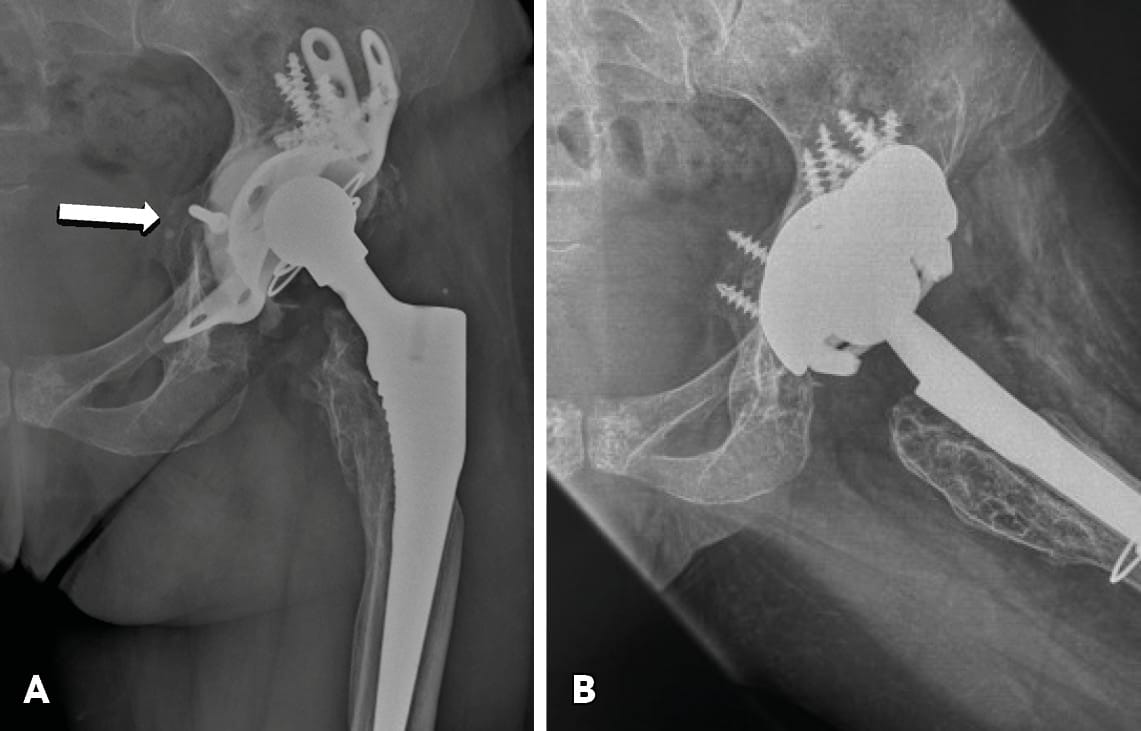

Tantalum cementless acetabular cups with augments. TM and related (e.g. Cription) technology acetabular components fixed with multiple holes superiorly and inferiorly (ilium, pubic and ischial rami) in combination with augments have recently been used in severe acetabular defects and chronic PD, especially in those with good bone stock (Figure 5b).[14] Batuyong ED, Brock HS, Thiruvengadam N, Maloney WJ, Goodman SB, Huddleston JI. Outcome of porous tantalum acetabular components for Paprosky type III and IV defects. J Arthroplsty. 2014; 28: 1318-1322. Implants made of highly porous structural materials (e.g. Tantalum and Cription) have demonstrated an improved friction coefficient for initial stability and better bony ingrowth for late stability. Early and mid-term outcomes are encouraging, allowing for extending the indications for their use (Figure 6).[15] Jenkins DR, Odland AN, Sierra RJ, Janssen AD, Lewallen DG. Minimum dive year outcomes with porous tantalum acetabular cup and augment construct in complex revision total hip arthroplasty. J Bone Joint Surg Am. 2017; 99:e49.

Cup and cage construct. This technique involves the placement of a highly porous Tantalum jumbo acetabular cell or cup against the host bone, bridging the acetabular defect. On the top of the cell, a special inlay cage is placed which spans the defect and is fixed into the ilium and ischium.[16] Hanssen AD, Lewallen DG. Modular acetabular augments: composite void fillers. Orthopaedics. 2005; 28:971-972. Tantalum augments are also used when necessary. “Half” cup cage reconstruction (removing the distal flange from the “full” cup-cage construct in order to address technical problems with its distal insertion) has also been introduced.[17] Sculco PK, Ledford CK, Hanssen AD, Abdel MP, Lewallen DG. The evolution of the cup-cage technique for major acetabular defects: ull and half cup-cage reconstruction. J Bone Joint Surg Am. 2017; 99:1104-1110. Mid-term outcomes are favourable and this technique has gained in popularity.[18], Amenabar T, Rahman WA, Hetaimish BM, Kuzyk PR, Safir OA, Gross AE. Promising mid term results wit a cup and cage construct for large acetabular defects and pelvic discontinuity. Clin Orthop relat Res. 2016; 474:408-414.[19] Conan S, Dunscan CP, Masri BA, Garbuz DS. The cup-cage reconstruction for pelvic discontinuity has encouraging patient satisfaction and functional outcome at median 6 years follow up. Hip Int. 2017; 27(5):509-513.

Triflange and tumour like custom made acetabular impants. Modern technology allows the production of personalised implants for special conditions. These type of implants are custom made, porous coated titanium implants and are considered the last therapeutic salvage option, before excisional arthroplasty, for severe acetabular defects and PD. The implants are designed and manufactured based on pelvic models created by thin-slice pelvic 3-D CT-scans with metal subtraction software (Figures 7 and 8). Early and mid-term outcomes are encouraging but premium cost and length of production time limit their use.[20], DeBoer DK, Christie MJ, Brinson MF, Morrison JC. Revision total hip arthroplasty for pelvic discontinuity. J Bone Joint Surg Am. 2007; 89(4):870-876.[21], Taunton MJ, Ferhing TK, Edwards P, Bersasek T, Holt GE, Christie MJ. Pelvic discontinuity treated with custom triflange component: a reliable option. Clin Orthop Relat res. 2012; 470(2):428-434.[22] Zhang Y, Gao Z, Zhang B, Du Y, Ma H, Tang Y, Liu Y, Zhou Y. The application of custom-made 3D-printed titanium augments designed through surgical simulation for severe bone defects in complex revision total hip arthroplasty. J Orthop Traumatol. 2022; 6:23(1):37.